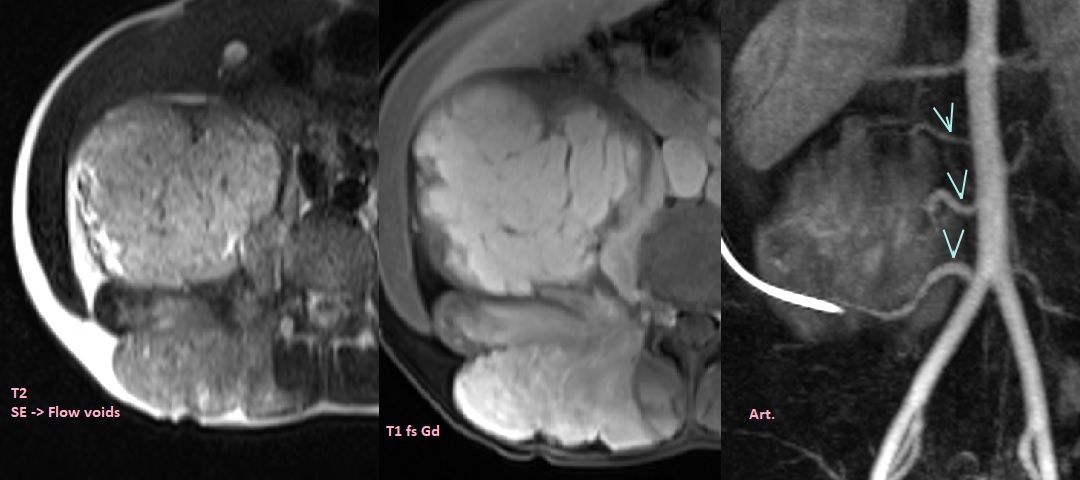

Phase proliférative

- Masse bien définie hyperT2 hypoT1

- Flow Voids

- Réhaussment homogène

MAV et Fistules-AV

Imagerie

- Vaisseaux nourriciers et de drainage seprigineux de claibre élargies avec remplissages précoce

- Présence de flow voids sur les séquences SE, (Les flows voids se voient en SE mais sont en hypersignal sur les GRE et prennent le contraste, contrairement aux phlébolites)